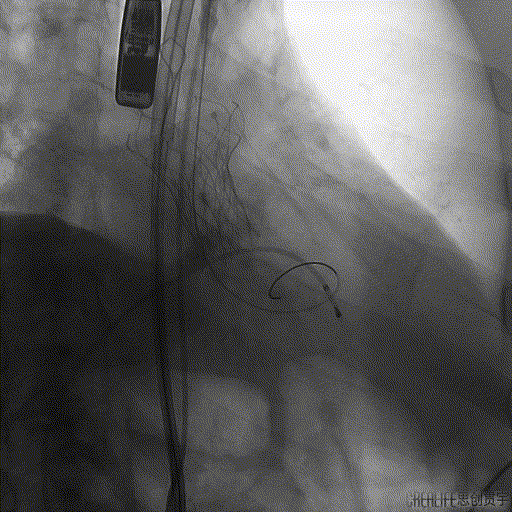

术中DSA影像

SENTINEL捕获并移除的碎片

张小卫教授在SENTINEL成功应用后表示:脑卒中是所有结构手术中一直非常头疼的问题,目前阶段会优先考虑在高龄,动脉硬化严重的TAVR以及二尖瓣狭窄患者中应用SENTINEL抗栓塞脑保护装置,其通过性和容忍度都非常优秀。该例患者虽然解剖复杂困难,但是整个操作相对简单仅用时3min即顺利成功植入,并且捕获到血栓,对于结构手术的安全保护作用意义深远。